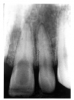

Figure 1 is a molar bitewing radiographic image that discloses a defective abutment restoration on tooth #4. The restoration ends short leaving open margins.

Figure 1 - Defective Restoration; Abutment Tooth #4

Figure 1